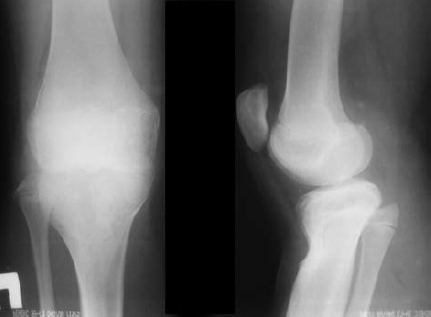

Рекурвация, Х-образные ноги

Только за несколько последних дней ко мне обратились несколько мам с вопросом рекурвации коленного сустава у детей. Откуда берется и как лечится это умное слово? И нужно ли вообще лечить?

Чаще всего у детей такие ноги “берутся” от родителей. Это вариант, который, как правило, не приводит к патологическим изменениям.

Причиной таких изменений могут быть еще и особенности внутриутробного развития.

Первое, что может сделать родитель - это поставить ребенка ровно, чтобы стопы стояли на одной линии по фронту. Если колени вашего ребенка соединены, а между стопами входит ладонь мамы, то в такой ситуации волноваться еще рано. Просто наблюдайте за ребенком и покупайте ему хорошую обувь. Скорее всего, при увеличении нагрузки и с ростом ноги выпрямятся. Но если между стопами расстояние равно ширине стопы ребенка, то тут нужно обратиться к ортопеду. И даже в такой ситуации стоит несколько раз подумать, прежде чем применять специальные устройства, ограничивающие движения ребенка. Тут надо все обсуждать с ортопедом, а еще лучше - собрать мнение нескольких специалистов. Это касается Х-образных ног у ребенка.